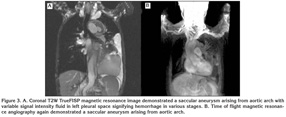

Computed tomography (CT) scan revealed a saccular aneurysm arising from the lateral aspect of the mid-transverse arch of the aorta, along with a dissecting descending aortic aneurysm (Figure 1, 2). An intimal flap was seen separating the true lumina and false lumina, which communicated with the left pleural space. The presence of hyperdense fluid in the left pleural space signified a leaking aortic aneurysm. Magnetic resonance imaging (MRI) was done which confirm the nature of lesion (Figure 3).

Figure 3